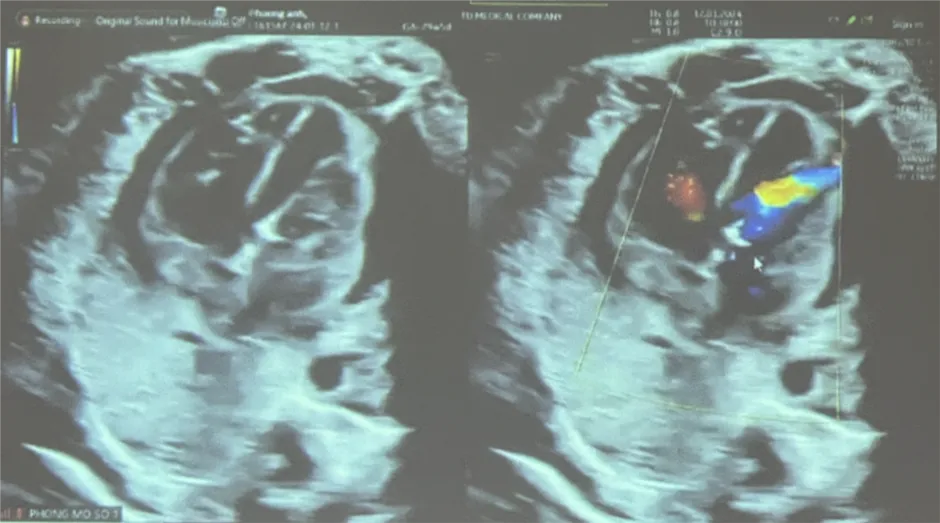

Đến ngày 11/1/2023, thai được 29 tuần với diễn tiến hẹp van động mạch chủ nặng, đường kính van 2.6 mm, vận tốc máu qua van động mạch chủ 300cm/s, gây thiểu sản thất trái nặng hơn, trào ngược van 2 lá mức độ nặng.

Đến 11 giờ, ca phẫu thuật kết thúc và thành công tốt đẹp. Thai phụ được theo dõi sát sau phẫu thuật, đến 13 giờ ngày 12-1, tràn dịch màng ngoài tim thai đã được kiểm soát tốt, nhịp tim thai bình thường, tình trạng sản phụ ổn định